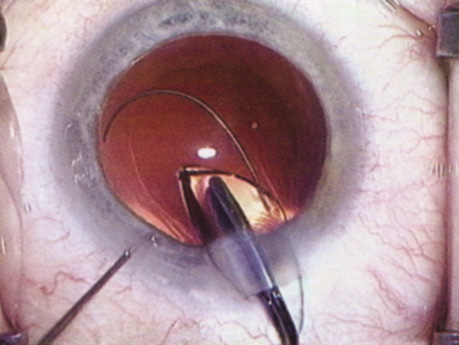

Hydrodissection can be performed after the surgeon has successfully completed capsulorrhexis.97 If the capsulorrhexis is not intact, fluid forced around the interior of the capsule may cause the bag to splay open. With capsulorrhexis, hydrodissection is a safe and extremely useful maneuver. Hydrodissection can be thought of as two maneuvers: hydrodelineation and cortical cleaving hydrodissection. By placing a 27-gauge cannula on a syringe filled with balanced saline solution (BSS), the surgeon can direct fluid beneath the residual anterior capsular rim to create a cleavage plane. Depending on the direction the fluid wave takes, different lamellae of the cataract will be separated. Hydrodelineation is the term used when the cleavage plane separates the adult nucleus from the fetal nucleus or the adult nucleus from the more peripheral epinucleus. Hydrodelineation often results in the characteristic golden ring sign (Fig. 11). Cortical cleavage occurs when the cortex is separated from the capsular bag (Fig. 12). Finding the cortical cleavage plane may be facilitated by gently lifting the capsular margin away from the cortex with the BSS cannula before injecting. Several small bursts of fluid allow the surgeon to monitor progress of the fluid wave. When dealing with a soft nucleus, the authors strive to perform true cortical cleaving hydrodissection. For a hard nucleus, hydrodelineation allows manipulation of less of the nuclear bulk, although the remaining epinuclear shell must be addressed in an additional step. Hydrodelineation is particularly useful if the nucleus is not freely mobile after cortical cleaving hydrodissection.

Fig. 11. A crisp “golden ring” is seen from the fluid cleft between the epinucleus and nucleus with hydrodelineation.